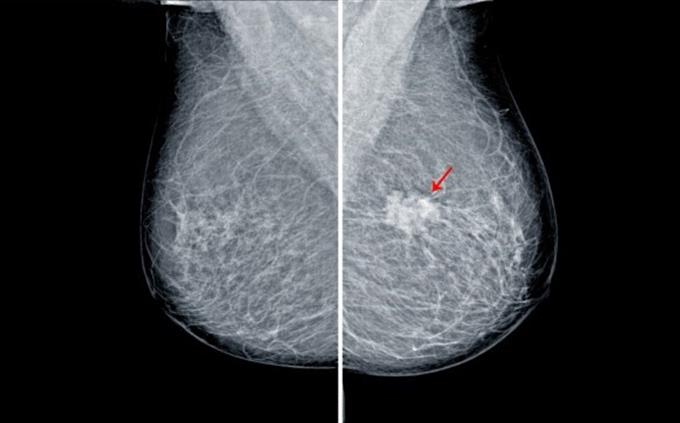

Mammography is specifically optimized to detect...

Breast microcalcifications